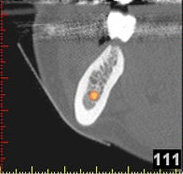

(siehe Bild 3 und 4).

Mit diesen gewonnenen Informationen und Planungen stellt der Zahnarzt interaktiv spezielle Bohrschablonen her. Diese ermöglichen eine exakte Positionierung der Implantate, so wie vorher am Computer geplant.